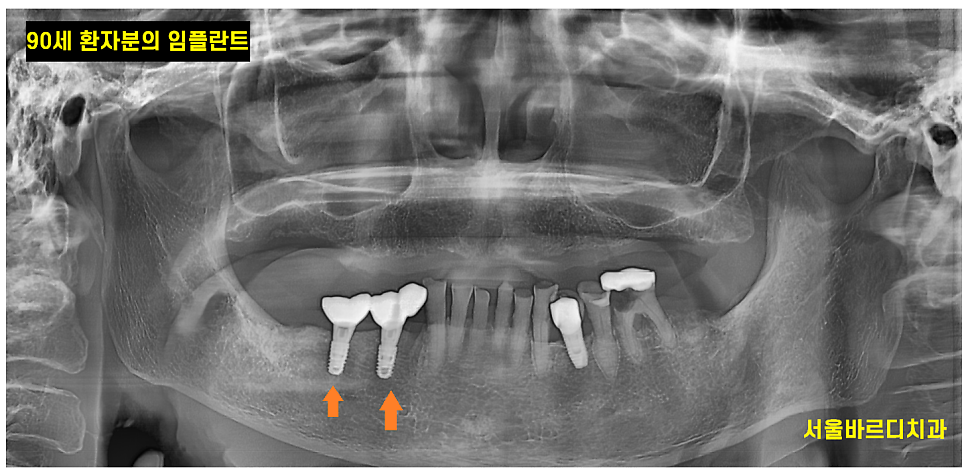

80대 90대 임플란트는 가능할까??

이번에는 반대로...

많은 환자분들이 나이가 너무 많아서

임플란트 수술에 대한 부담감을 많이 갖고 계십니다.

되도록 수술은 피하고 싶어하시죠~

나이가 많은 노년층 환자분들도

건강 상태만 허락하면 임플란트 치료가 충분히 가능해요~

241024

수면마취나 전신마취로 진행하는게 아니라

부담이 적고